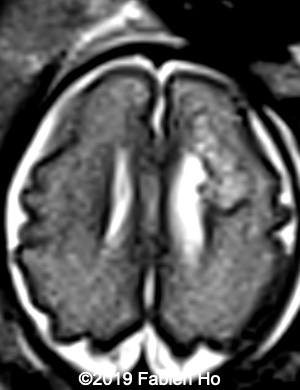

Images 1-3: in the left frontal lobe, hyperechoic with hypoechoic center lesion within the deep and periventricular white matter. Interestingly, this lesion has no mass effect on the lateral ventricle, and it has smooth margins.

Images 4-11, fetal brain MRI at 28 weeks: the left frontal lesion hence shows DWI hyperintensity, with T2* and T1 peripheral hyperintensity: ischemia with peripheral subacute hemorrhage. Note also that there is an associated blood clot in the left lateral ventricle. There is no obvious mass effect, nor peripheral edema. All these findin>gs are very suggestive of a clastic lesion.

Axial T2w

4

5